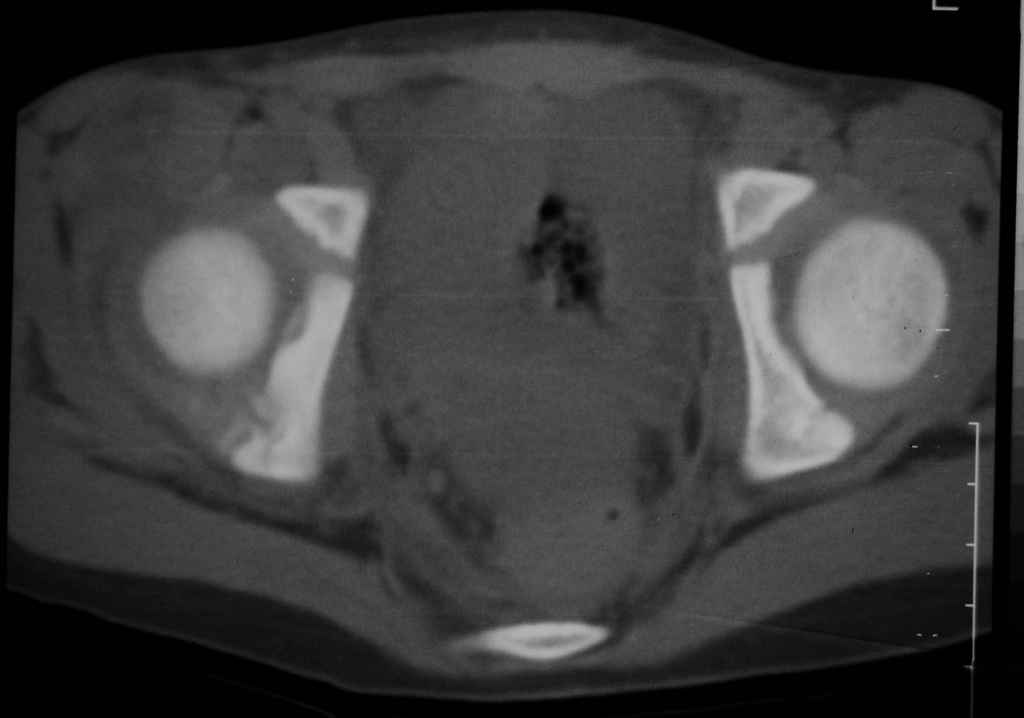

Перелом вертлужной впадины

Уважаемые коллеги, помогите определиться с тактикой лечения.Ребёнок 7 лет, травма 11.09.08, поступил с травматическим вывихом бедренной кости.

Вывих вправлен, конечность фиксирована на скелетном вытяжении. Что делать с переломом подвздошной кости? Лечить консерватино или оперировать?